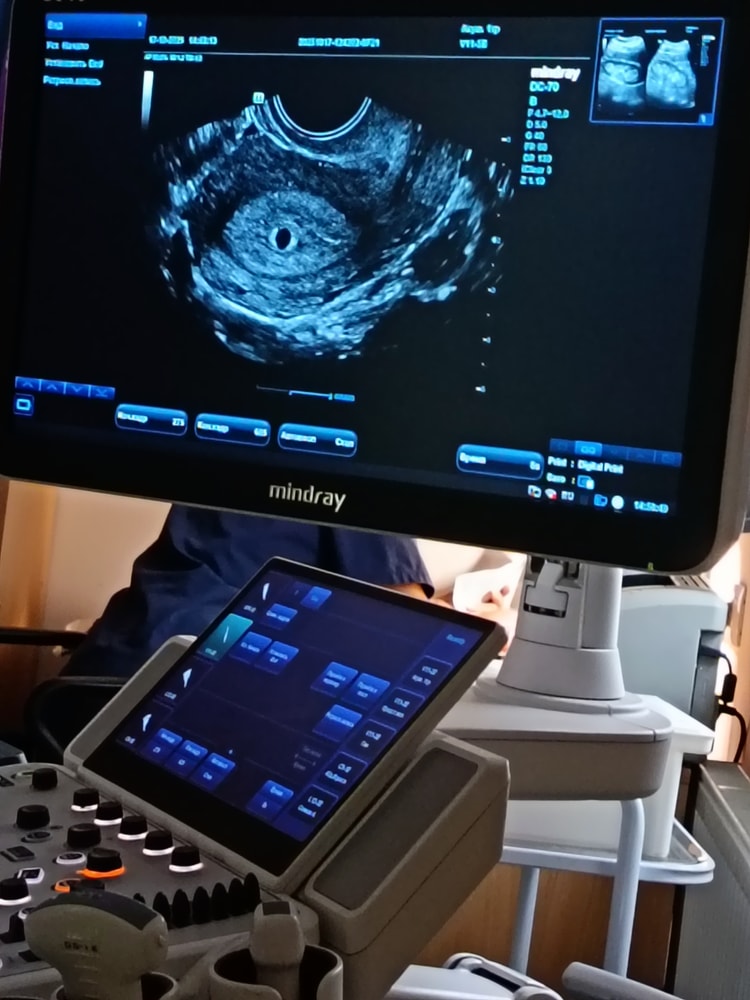

Нет, на раннем сроке гипертонус передней стенки матки

не является нормой и требует обязательного обращения к врачу, поскольку может указывать на угрозу выкидыша или другие осложнения. Врач должен оценить состояние, выяснить причину и назначить соответствующее лечение, которое может включать медикаментозную терапию и постельный режим.

И киста там есть …. Что вам врач сказал по поводу узи вашего ?